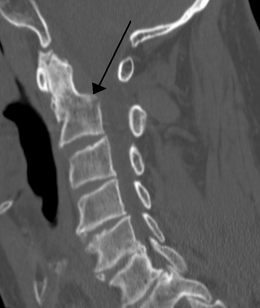

Ancien Responsable Matière Hypnos Posted May 4, 2020 Ancien Responsable Matière Posted May 4, 2020 le bord est convexe mais par la surface en elle même regarde, elles sont nettement concave vers le bas sur cette radio Quote

Solution YoungCalvitie Posted May 4, 2020 Solution Posted May 4, 2020 @Petit_Bateau @Paracelse bonjour ! Attention, le prof fait bien la distinction lorsqu'il décrit la partie centrale du spondyle et ses bords. En effet, il y a 2 choses bien distinctes: - Au centre du corps vertébral, la surface est concave. cela vaut pour sa face supérieure et sa face inférieure. comme l'a dit @Petit_Bateau, cela permet l'accueil du DIV. - Sur la périphérie du corps, en cervical, il y a la présence d'un système crochet/biseaux sur les parties latérales des corps. Si on regarde de face, le biseau sur le pourtour de la surface inférieure donne une concavité en haut. A l'imagerie au scanner (et non radiographie), on remarque plutôt la concavité centrale des spondyles. Pour se rendre compte du système crochets/biseaux, il faudrait plutôt rechercher un scanner de face comme celui-ci Alors on se rend compte que les surfaces antéro-latérales (ou postéro-latérales c'est indifférenciable sur ce cliché) comportent une concavité vers le haut, et c'est les crochets et les biseaux situés latéralement. En espérant avoir pu aider, N'hésitez pas si besoin Quote